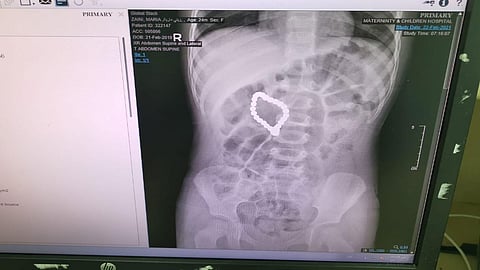

تمكن فريق طبي في مستشفى الولادة والأطفال بمكة عضو تجمع مكة المكرمة الصحي من إنقاذ حياة طفلة تبلغ من العمر عامين، ابتلعت كمية من كرات مغناطيسية.

وكانت الطفلة وذووها حضروا إلى طوارئ الأطفال تعاني من توعكات، وبعد الكشف اتضح وجود جسم غريب عندها قرر الفريق الطبي المكون من استشاري جراحة الأطفال الدكتور تركي رشاد آمين واستشاري جهاز هضمي أطفال الدكتور عبدالله الشمبري في التدخل عن طريق المنظار الجراحي، وتم استخراج 3 كور مغناطسية إلا أن بقية الكور كانت متداخلة في جدار البطن وجدار بداية الأمعاء.